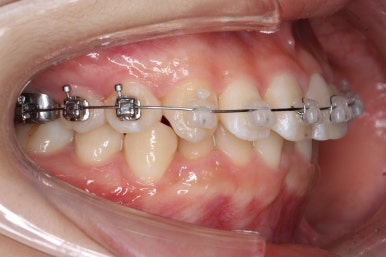

연산동교정치과에서 이번에 사용한 장치는 데이몬 클리어라고 하는 자가결찰 세라믹 장치입니다. 현재 붙이는 장치 중에서 세라믹의 비율이 가장 높아 치아색과 가장 유사한 장치입니다.

우선 윗니부터 가지런하게 합니다. 그리고 아랫니는 가지런하게 할 준비를 하죠.

화살표에 보이는 부착물의 이름이 바이트터보 입니다.

깊게 맞물리는 앞니, 즉 과개교합을 개선하기 위해 일시적으로 이용하는 장치입니다.

굉장히 효율적으로 과개교합을 개선할 수 있습니다.

아랫니에도 이제 장치를 붙였습니다.

과개교합인 채로 아랫니에도 장치를 붙이게 되면 아랫니 장치가 깨물려서 다 떨어지거나 부서지기 쉽습니다. 따라서 바이트터보는 굉장한 역할을 하게 됩니다.

연산동교정치과에서 이번에 진행한 방법은 비발치교정이기 때문에 미니스크류를 잇몸뼈에 식립합니다.

위 사진에서 화살표 부분이 미니스크류인데요.

어금니쪽 잇몸에 아주 작은 나사가 보이실텐데요. 이것을 이용해서 전체 치열을 뒤로 당겨넣습니다. 물론 사랑니는 제거가 된 상태입니다.